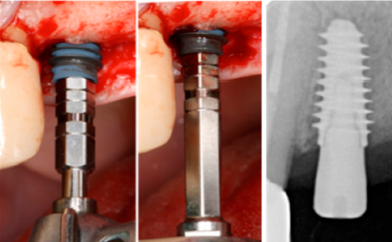

Onze kerngebieden van onderzoek omvatten onder andere implantaatmaterialen, biomaterialen, digitalisering, prothetiek, tandtechniek, nazorg, peri-implantitis, en patiëntspecifieke behandelingen. Heb jij een idee voor een onderzoek waarmee je bouwt aan de toekomst van de orale implantologie? Stuur ons jouw voorstel en wij nemen contact met je op om te overleggen waar we je kunnen ondersteunen.